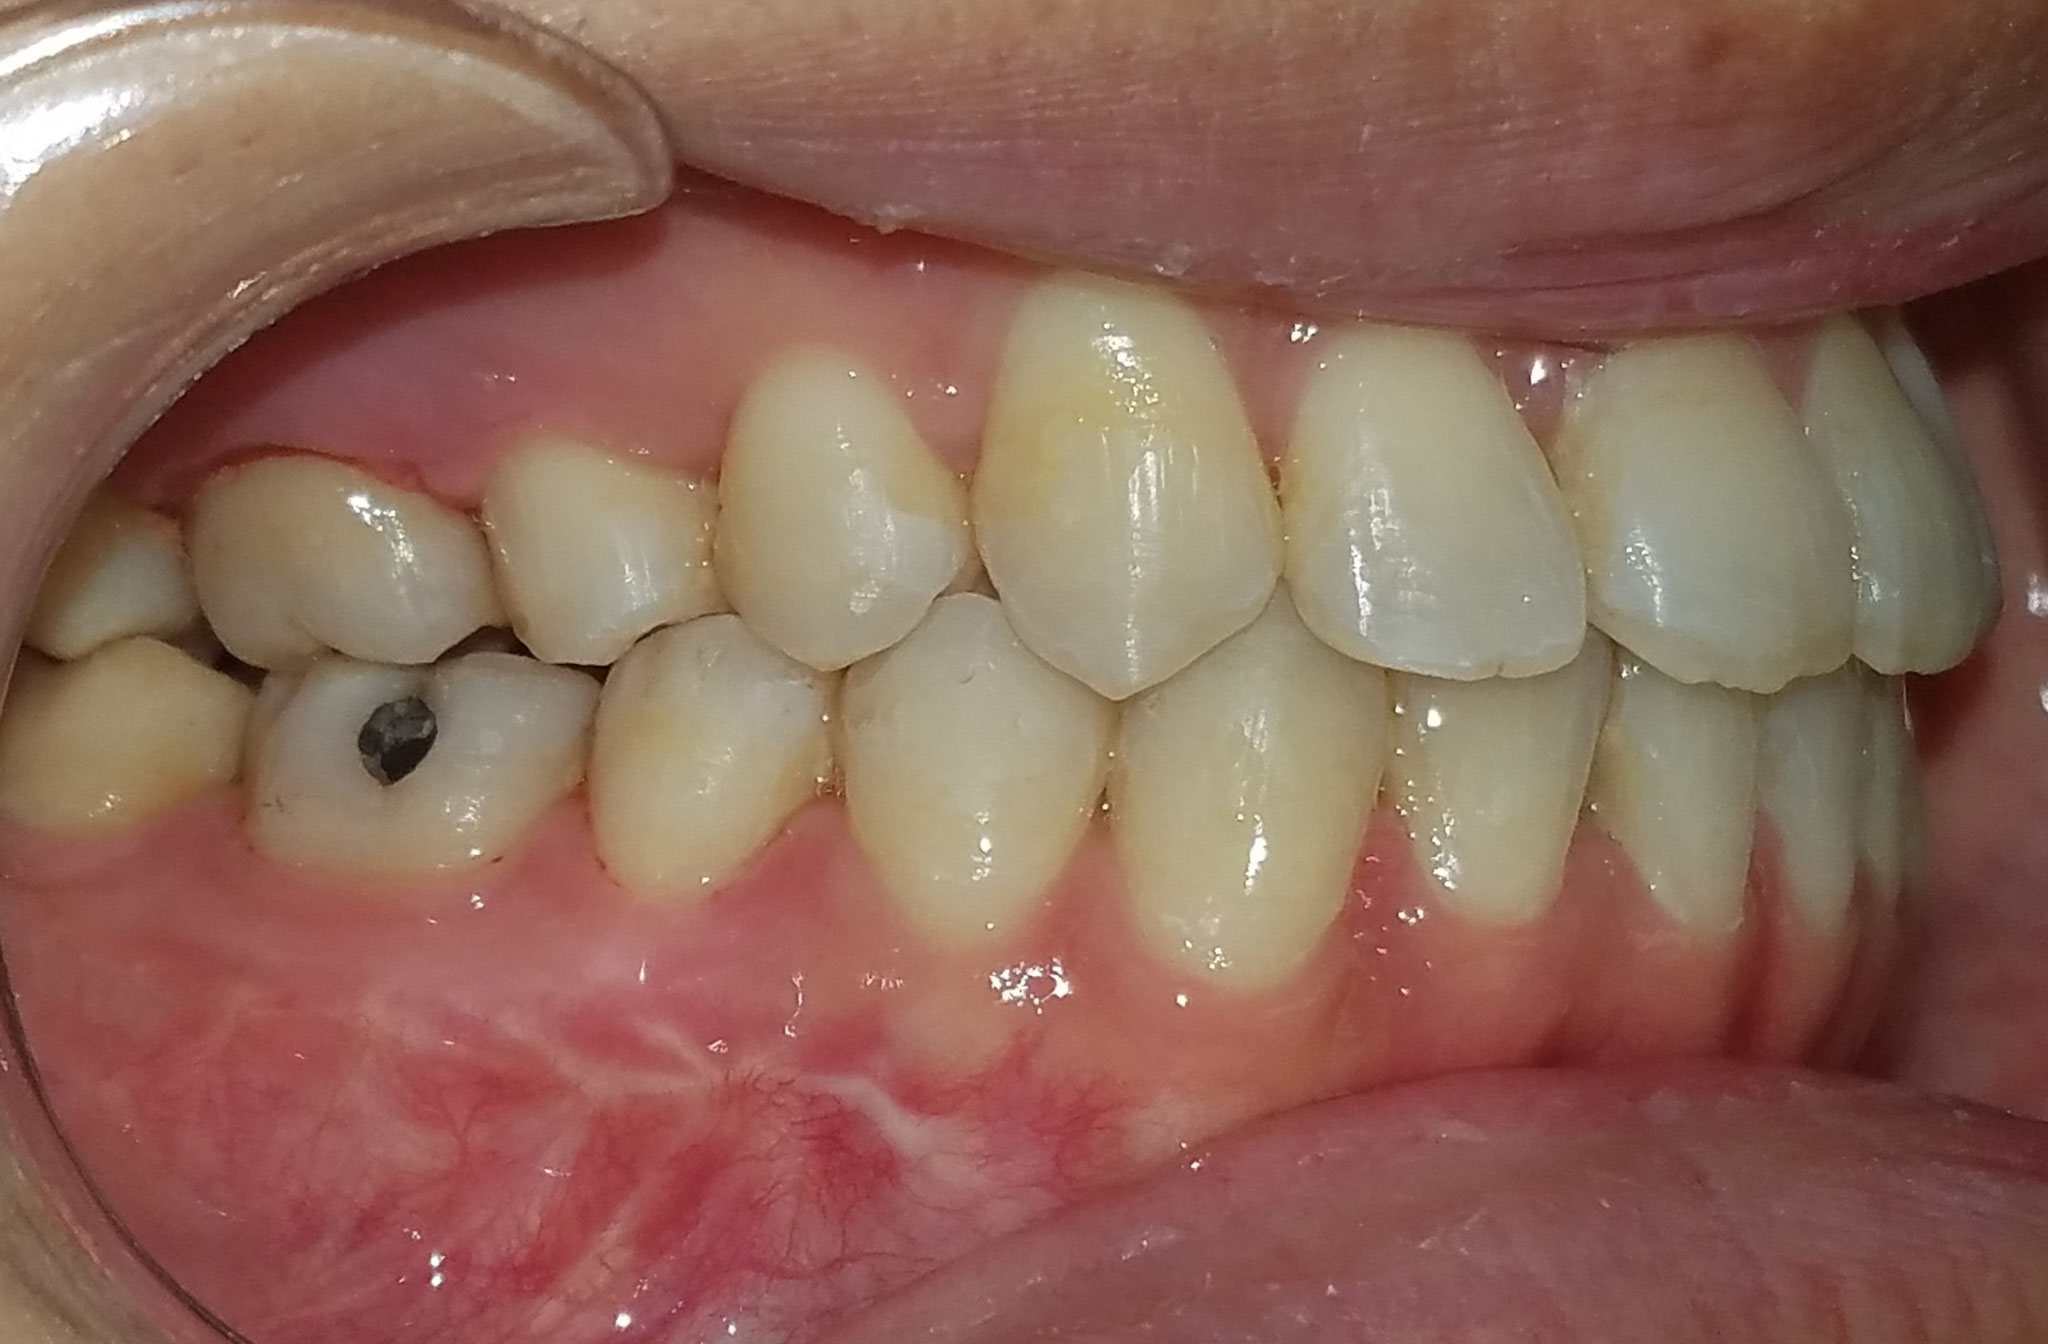

From yangorthodontics.com

One of our patients at Yang Orthodontics had a severe underbite Orthodontics And Orthognathic Jaw Surgery The length of your actual surgery is approximately two to three hours per jaw. Jaw surgery, also called orthognathic surgery, is surgery that helps align your upper jaw (maxilla) and lower jaw (mandible). A guide for patients considering orthodontics and jaw surgery (orthognathic treatment). They may include orthognathic, which refers to the causes and treatment of bones. Orthognathic surgery is. Orthodontics And Orthognathic Jaw Surgery.